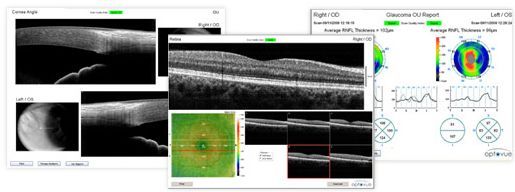

С 21 июня 2010 года в МК ЦЭЛТ можно выполнить данное исследование на новейшем оптическом когерентном томографе RTVue (США), который позволяет получить неинвазивным способом изображение ткани сетчатки in-vivo, с высокой скоростью сбора данных и сканами с высоким разрешением.